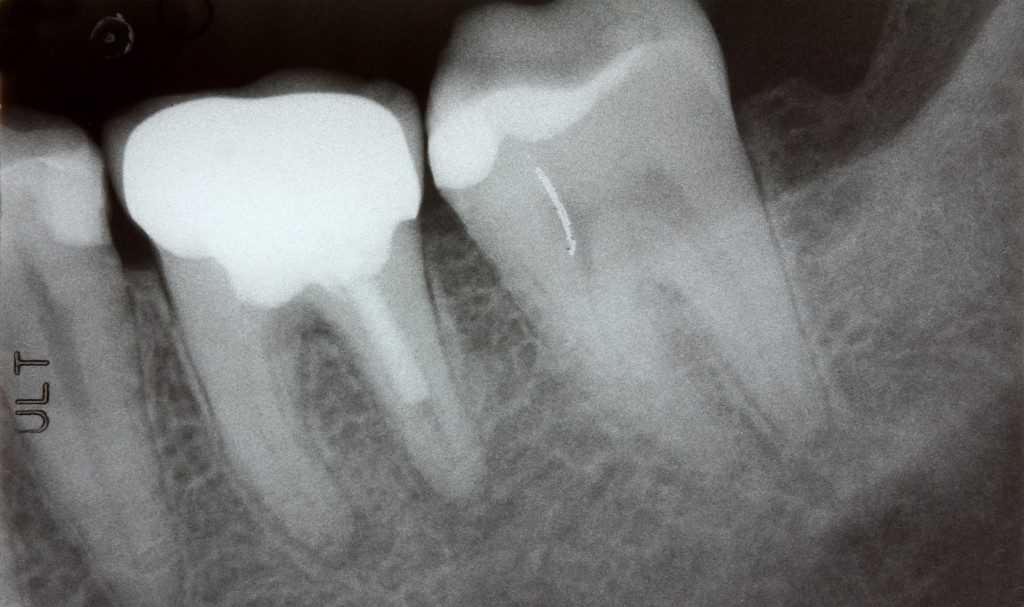

Penelitian terbaru menunjukkan bahwa penyakit gusi yang dikenal sebagai periodontitis dapat meningkatkan risiko gangguan irama jantung atrial fibrilasi (AFib) hingga 30 persen. Hal ini disebabkan oleh bakteri mulut berbahaya yang dapat menyebar dari gusi ke jantung melalui aliran darah.

Studi pada tikus yang diinfeksi bakteri Porphyromonas gingivalis mengungkap bahwa bakteri ini dapat masuk ke bagian atrium kiri jantung, menyebabkan pembentukan jaringan parut yang mengganggu sinyal listrik jantung, sehingga meningkatkan kemungkinan AFib.

Peneliti juga menemukan bakteri ini pada jaringan jantung pasien manusia yang menderita AFib, di mana jumlah bakteri sebanding dengan tingkat keparahan penyakit gusi mereka. Temuan ini menguatkan adanya hubungan langsung antara infeksi gusi dan kesehatan jantung.